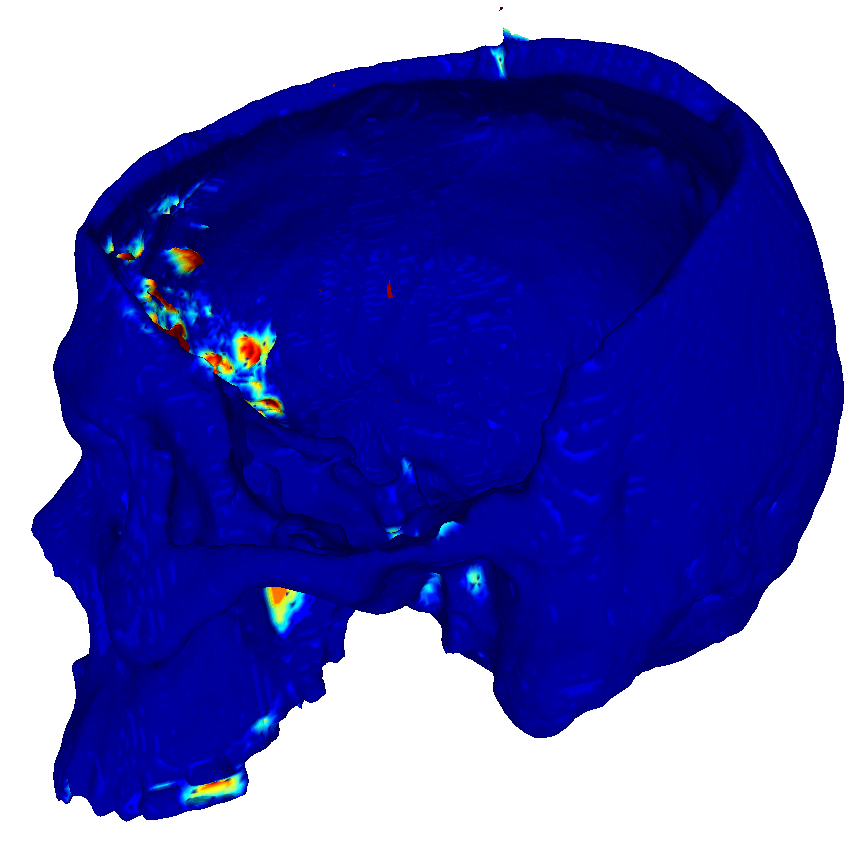

22 scans were randomly selected as test subjects for the experiment, leaving 177 skulls for model training. Using convolutional kernels of size 3 in all the CNN models results in the 3D model having the same number of trainable parameters as the sum of the three orthogonal 2D models. The comparison between the MV ensemble and the 3D approach can therefore be considered an ablation study to an extent. CutCNN models also have a similar number of parameters, the only difference being the final edge probability output layer. Quantitative comparison of results of each method are presented in Figure 4 and Table 1. Further qualitative results are shown in Figure 5 and 1.

CutCNN segmentation framework resulted in a performance gain in all cases in terms of every metric used in the experiment over standard CNN approaches. The output of CNN object probability map often contains errors near external objects or smaller tissue defects as these are scarce in the training data distribution. However, the graph-cut optimization guides the resulting binary segmentation towards a spatially consistent and compact shape, often eliminating these artifacts if a detected edge corresponds mostly to the correct object boundary. This effect is further illustrated in Fig. 1.